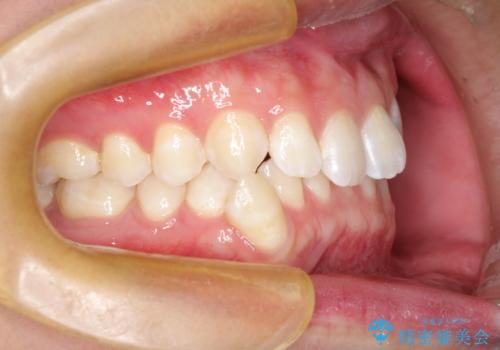

下の奥歯を後方へ移動させてスペースを確保して、前歯を並べる計画としました。

使用時間を守っていただけたので、比較的スムーズに矯正を終了することができました。